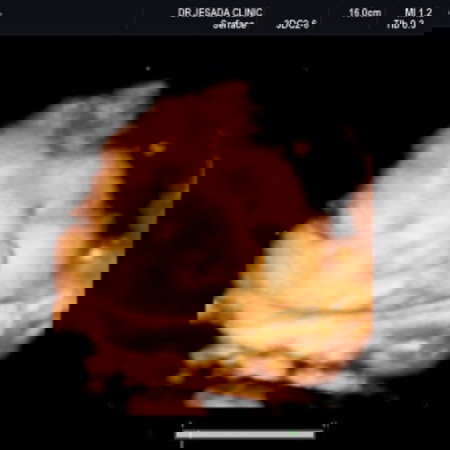

จ้ำม่ำมากค่ะแม่

หือ...สะออนแก้ม😊